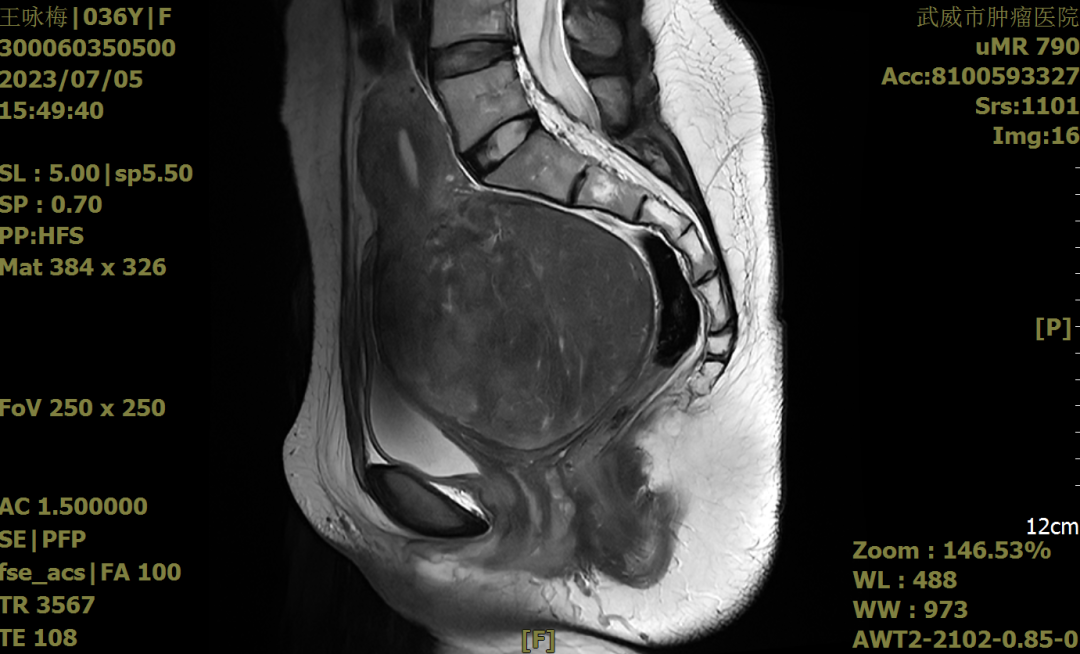

手术前我们再次确认患者的HPV检测阴性;宫颈TCT涂片:无上皮内病变或恶性病变(NILM)。血常规、肝功能、肾功能、心功能、肺功能等均无明显异常。B超、核磁共振检查(如下图)。

2023-7-5盆腔核磁(矢状位)

2022年7月8日栾桦主任带领我院王睿梅主任的妇科团队,在肚子上打了4个小孔,花了将近5小时的时间,用腹腔镜成功完成了王女士的肌瘤剔除手术,术中确认为宫颈中央型肌瘤,瘤体包围宫颈前壁、后壁及右侧壁,大小约11*10*10cm,术中边剔除边止血,尽可能的减少出血,因瘤体太大,压迫到右侧输尿管,为避免和预防术后输尿管瘘的发生,我们特意邀请泌尿外科协助放置了双侧输尿管J型导管。术后患者无任何手术并发症,术后病理提示子宫颈平滑肌瘤,术后8天王女士康复出院。